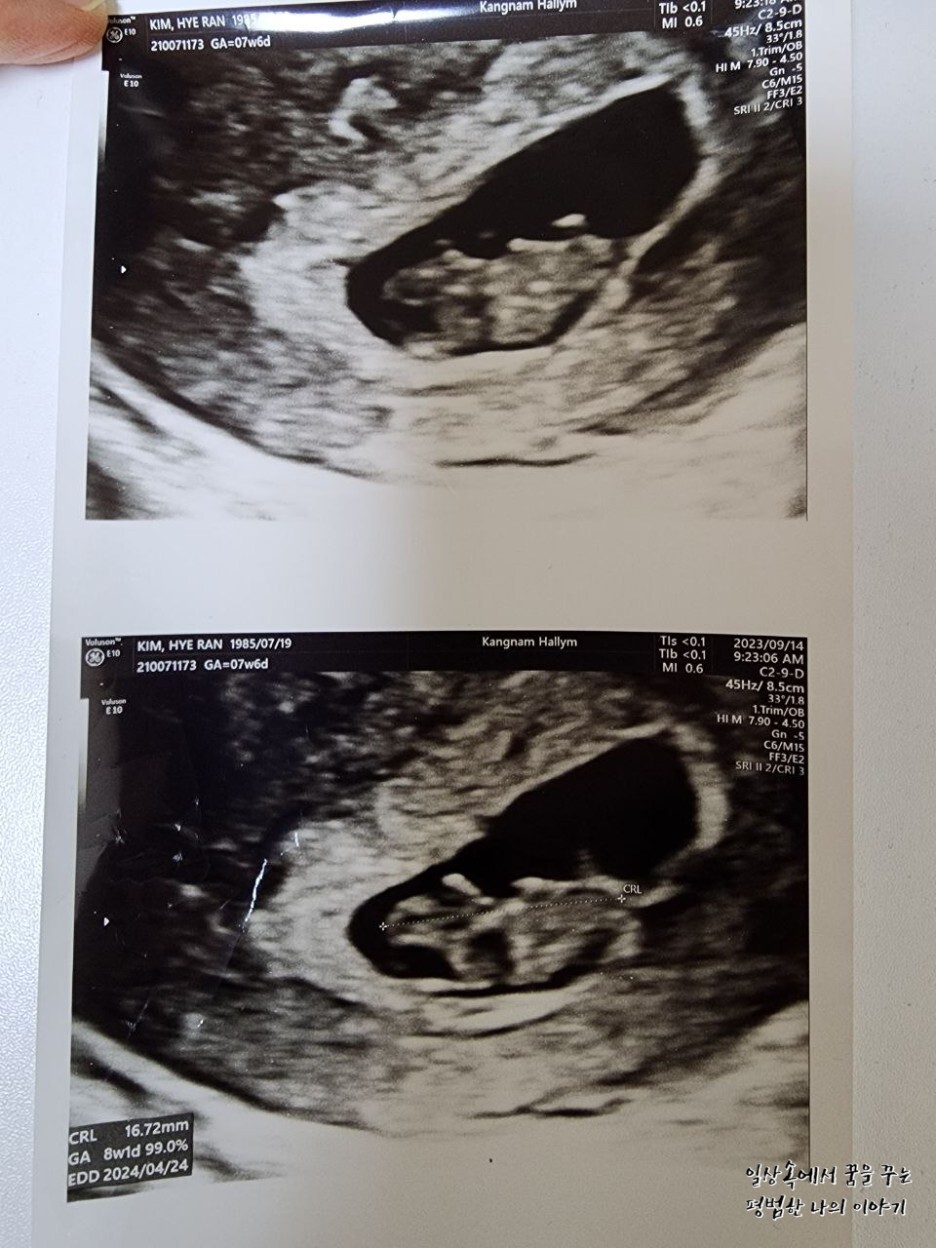

일주일 만에 다시 만난 레오나는 그 새 무럭무럭 자라 있었는데 너무나 귀여운 젤리 곰 모양을 하고 있었다.(초음파를 통해 젤리 곰 형태의 귀여운 태아를 볼 수 있는 주차 수는 보통 8~9주이므로 일부러 이때를 맞춰 산부인과에 방문하는 산모도 있다) 얼굴, 손 그리고 발의 형태를 모두 볼 수 있었는데 둘째인데도 여전히 내 뱃속에서 생명체가 자라고 있다는 사실은 늘 신기하다. 그리고 매번 산부인과에 방문해 성장해 있는 모습을 볼 때마다 감탄한다. 아무래도 첫째 육아를 하면서 임신 과정을 겪는 거라 첫째 임신 때보다 덜 조심하게 되고 덜 신경 쓰게 되고 산부인과도 덜 가게 돼서 항상 미안한 마음이 든다.

레오나의 CRL(=Crown-Rump Length, 태아의 머리부터 엉덩이까지의 길이)은 16.72mm로 평균보다 살짝 컸지만 원래 낳기 전까지 크기는 계속 변하기 때문에 크게 의미를 두지 않아도 될 것 같다.